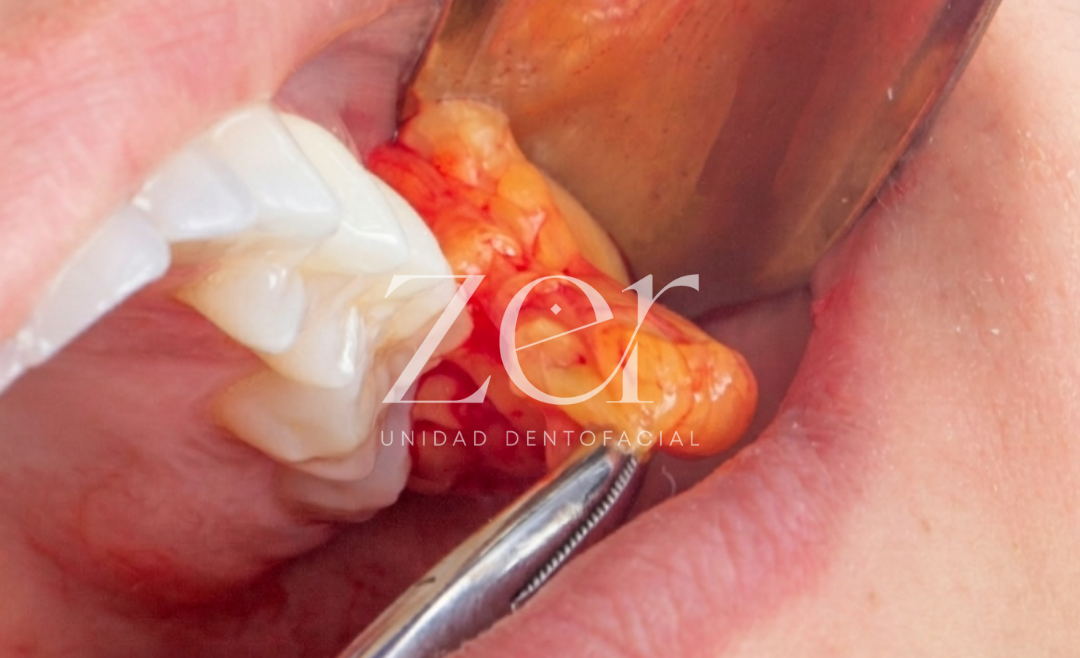

La frenillectomía, conocida también como frenectomía, es un procedimiento quirúrgico mínimamente invasivo, que consiste en la resección parcial o total del frenillo, que es una pequeña banda de tejido que conecta el labio superior o la lengua con la encía o el suelo de la boca, respectivamente.

Es una intervención quirúrgica que se realiza generalmente bajo anestesia local, pero, el tipo de sedación dependerá de la edad del paciente y la complejidad del caso. En bebés, generalmente se realiza bajo anestesia local, ya que el procedimiento es rápido y el área afectada es pequeña. En adultos, se puede usar la sedación endovenosa si el paciente es muy ansioso o el procedimiento es más complejo.

La intervención se puede realizar bajo anestesia local (principalmente) o con sedación endovenosa, y suele durar entre 15 a 30 minutos. La elección entre sedación endovenosa y anestesia local depende de varios factores, incluyendo la complejidad de la cirugía, la preferencia del cirujano y del paciente, y el estado de ansiedad del paciente.